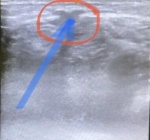

7. Боррелиоз или болезнь Лайма

Боррелиоз

Как ни странно, но и эта болезнь может привести мозг флеболога в активное состояние. Болезнь, открытая в 1970-ых и носящее название городка в Коннектикуте вызывается спирохетой. Стадийность болезни похожа на сифилис. Передается она через слюну иксодовых клещей, а ещё может при употреблении козьего молока от больного животного. Кожные покровы в основном на ногах изменяются как при панникулите и склеродермии. Системные проявления также характерны. Диагностика болезни по анализу крови, да и лечение антибиотиками - все это позволяет думать о хорошем результате. Но главным мне кажется не лечение а способность доктора заподозрить болезнь, когда острота прошла и нет указания на укус клеща. Вот где искусство врачевания!

Вероятно, что много пациентов ходит с этой болезнью и не знает причины кожных и других ее проявлений. Поражение кожи опять же в излюбленных зонах нарушения трофики при венозной недостаточности.

Фото слева от доктора Оксаны Букиной. Эта пациентка не помнила, что ее кусал клещ.

При укусе клеща не стоит ждать проявлений первичной реакции кожи в виде кольцевидной эритема. Лучше сразу начать превентивное лечение препаратами тетрациклинового ряда.

А вот и мое наблюдение на фото справа. У пациентки два месяца существует гиперемия, или эритема по внутренней поверхности правой голени. Указания на укус клеща не было. Но серологические реакции характерные для боррелиоза положительные.